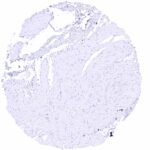

Comparison of antibodies: True expression of PODXL in all cell types with PODXL positivity by MSVA-645M is corroborated by an identical staining obtained by a commercially available independent second antibody (termed “validation antibody”). An additional staining of squamous epithelia by the validation antibody which was not seen by MSVA-645M was considered an antibody specific cross-reactivity of our validation antibody.